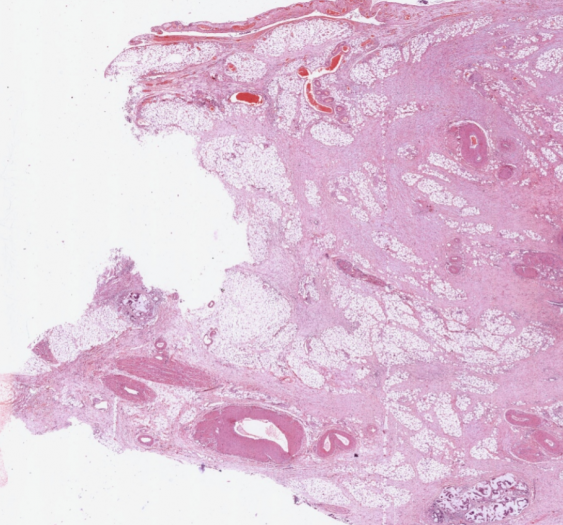

2、数字资源:划分有专门的数字资源模块,包含400多个精细的3D病理虚拟模型、700多个3D病理大体标本、50个手术入路解剖3D模型、400多张病理学数字切片、200多部临床 手术3D动画、30部病理学3D动画、100多部病理学数字切片微视频等资源,以震撼的视觉吸引力、丰富易读的知识点精彩呈现。